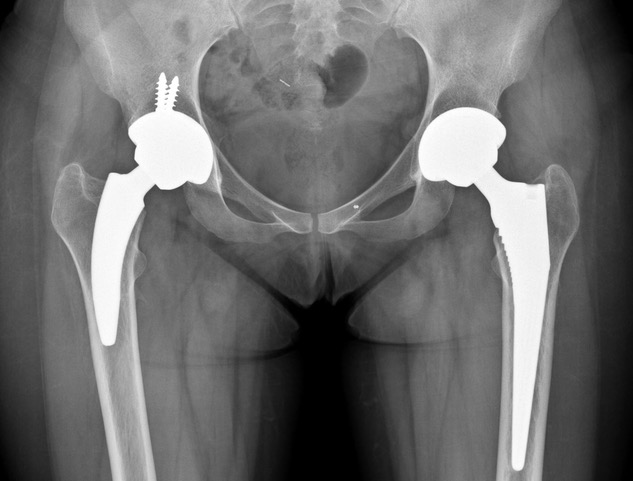

Reemplazo total de cadera con un tallo corto no cementado tipo 2B: resultados a los 2-5 años de seguimiento. [Total hip replacement with a short cementless stem type 2B: Results of 2 to 5 years of follow-up]